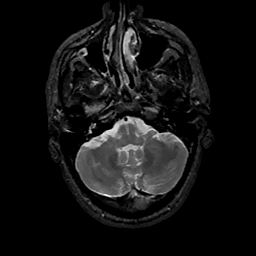

MR Study #11, May 5, 1991 -- Slice #10

[Home][Help][Clinical][Tour 1][Tour 2] Slice 10